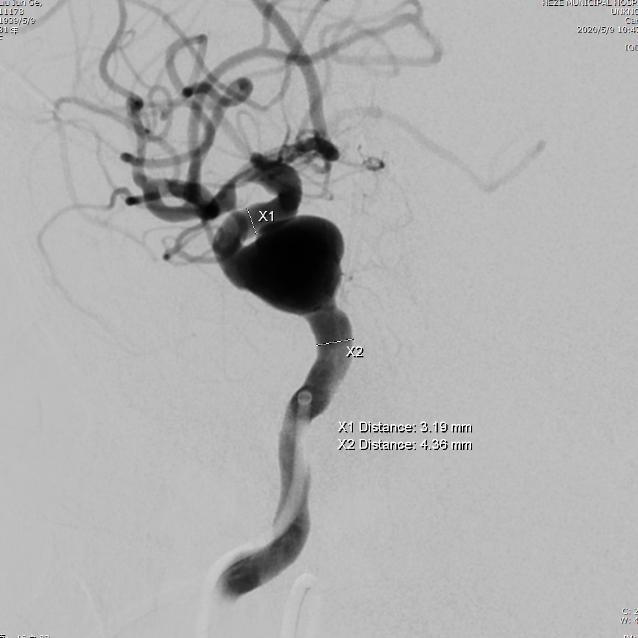

检查:经颅脑MR平扫+MRA检查考虑右侧海绵窦段动脉瘤。在局麻下行DSA,结果示:右侧颈内动脉海绵窦段动脉瘤;右侧颈内动脉C1段严重迂曲;右侧大脑中动脉M1段中度狭窄。

术前影像

术前测量:动脉瘤大小为12x11mm,瘤颈为13mm,动脉瘤远端血管直径3.8mm,近端血管直径4.5mm。